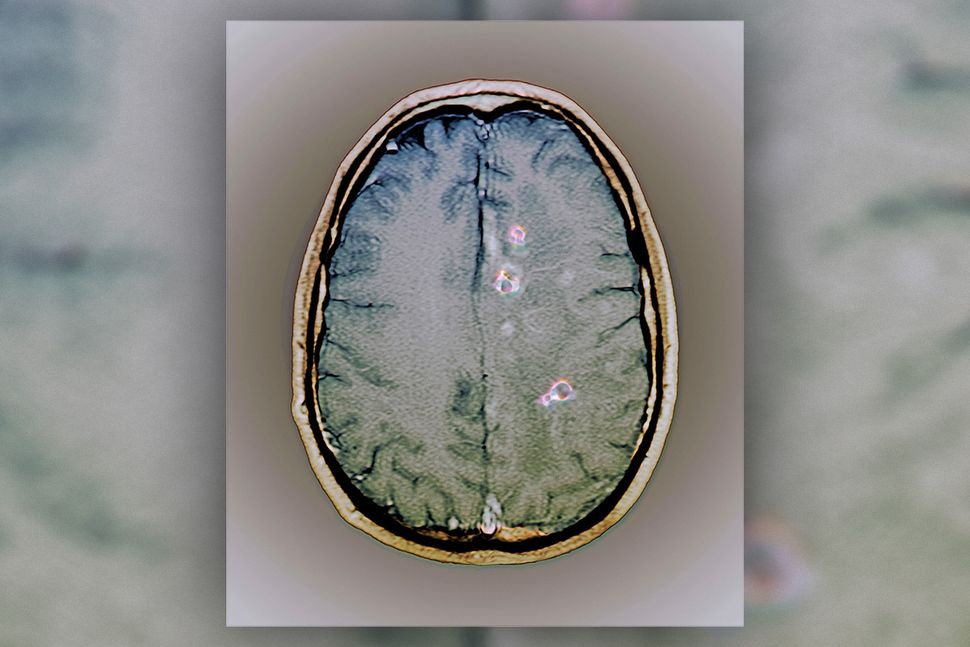

Tapeworm Cyst In The Brain, Mri Scan Photograph by Zephyr Tapeworm In Brain The parasites which are responsible include echinococcus granulosus and echinococcus multilocularis. Learn about tapeworm infection, a parasitic condition that can affect your intestines and other organs. The aches were caused by tapeworm. You may be referred to a doctor who treats problems in the brain and central nervous system, called a neurologist. The most common one is taenia solium, the. Tapeworm In Brain.